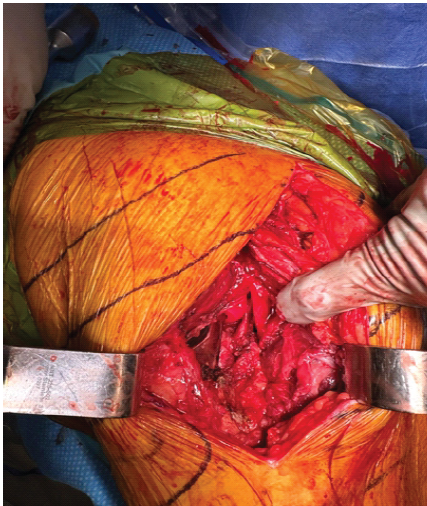

Given the failed reductions and the development of neurological deficits, the decision was made to proceed with an open reduction. During the procedure, it was found that the femoral head had penetrated through the gluteus medius muscle, impeding reduction (Fig. 2). In addition, the sciatic nerve was abutting the posterior acetabulum and was entrapped in scar tissue (Fig. 3).

Figure 2: Clinical photograph during open reduction with the head violating the abductors.

Figure 3: Clinical photograph during open reduction showing scarred sciatic nerve abutment against the posterior margin of the cup.

Neurolysis was performed to release the sciatic nerve, and the femoral head was carefully disengaged from the muscle. The acetabular and femoral prosthetic components were assessed and deemed to be stable and thus were left in position. The femoral head size was increased from +4 to +8 (32 mm head) to enhance stability (Figs. 4 and 5).

This case illustrates several critical challenges in managing periprosthetic dislocations. The perforation of the femoral head through the gluteus medius is a rare mechanical impediment to reduction but should be suspected when numerous attempts have failed. In addition, sciatic nerve entrapment, likely due to scarring, compounded the difficulty in achieving a closed reduction and provided additional challenges in the post-operative period. Irreducible dislocations, though rare, present unique clinical difficulties. Previous literature states failed closed reductions could be due to entrapment of the iliopsoas tendon, interposition of the joint capsule, cement fragments, or other third-body elements [4,8,9,10,11]. Non-concentric reductions during attempts at closed reduction should alert the surgeon to the possibility of such interpositions necessitating open reductions. In addition, sciatic nerve complications – though with a prevalence of <0.1% – can occur, further complicating management [14]. Due to the proximity of the sciatic nerve to the posterior hip structures places it at risk of tension or compression injury during reduction maneuvers [13,14]. Cases of sciatic nerve entrapment around the femoral stem following closed reduction have been documented but are very limited in the literature [12,13,14,15,16,17]. When sciatic nerve palsy occurs post-reduction, immediate surgical exploration and neurolysis may be warranted to prevent permanent motor deficits [12]. This underscores the importance of limiting forceful reduction attempts and performing neurovascular assessments following manipulative efforts. It is recommended to monitor partial and secondary nerve injuries with an initial observation period of four to 6 months, as spontaneous recovery occurs in 70–100% of cases [14].